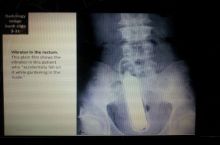

It's lil wayne's newest single.